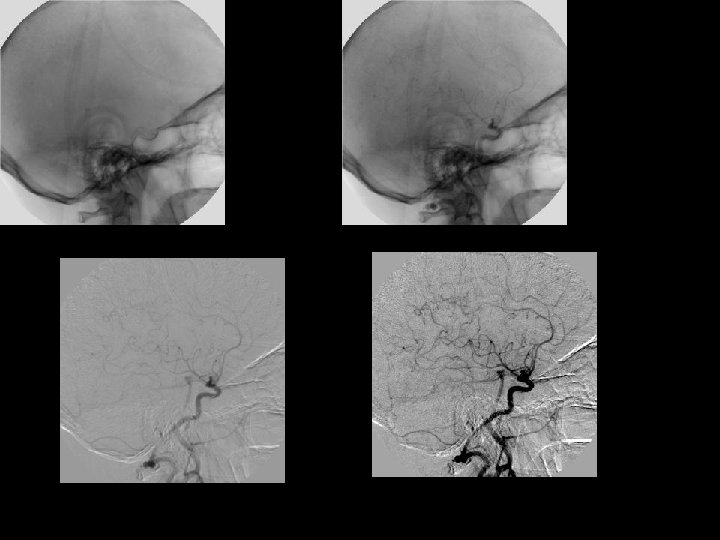

43 Which system ?